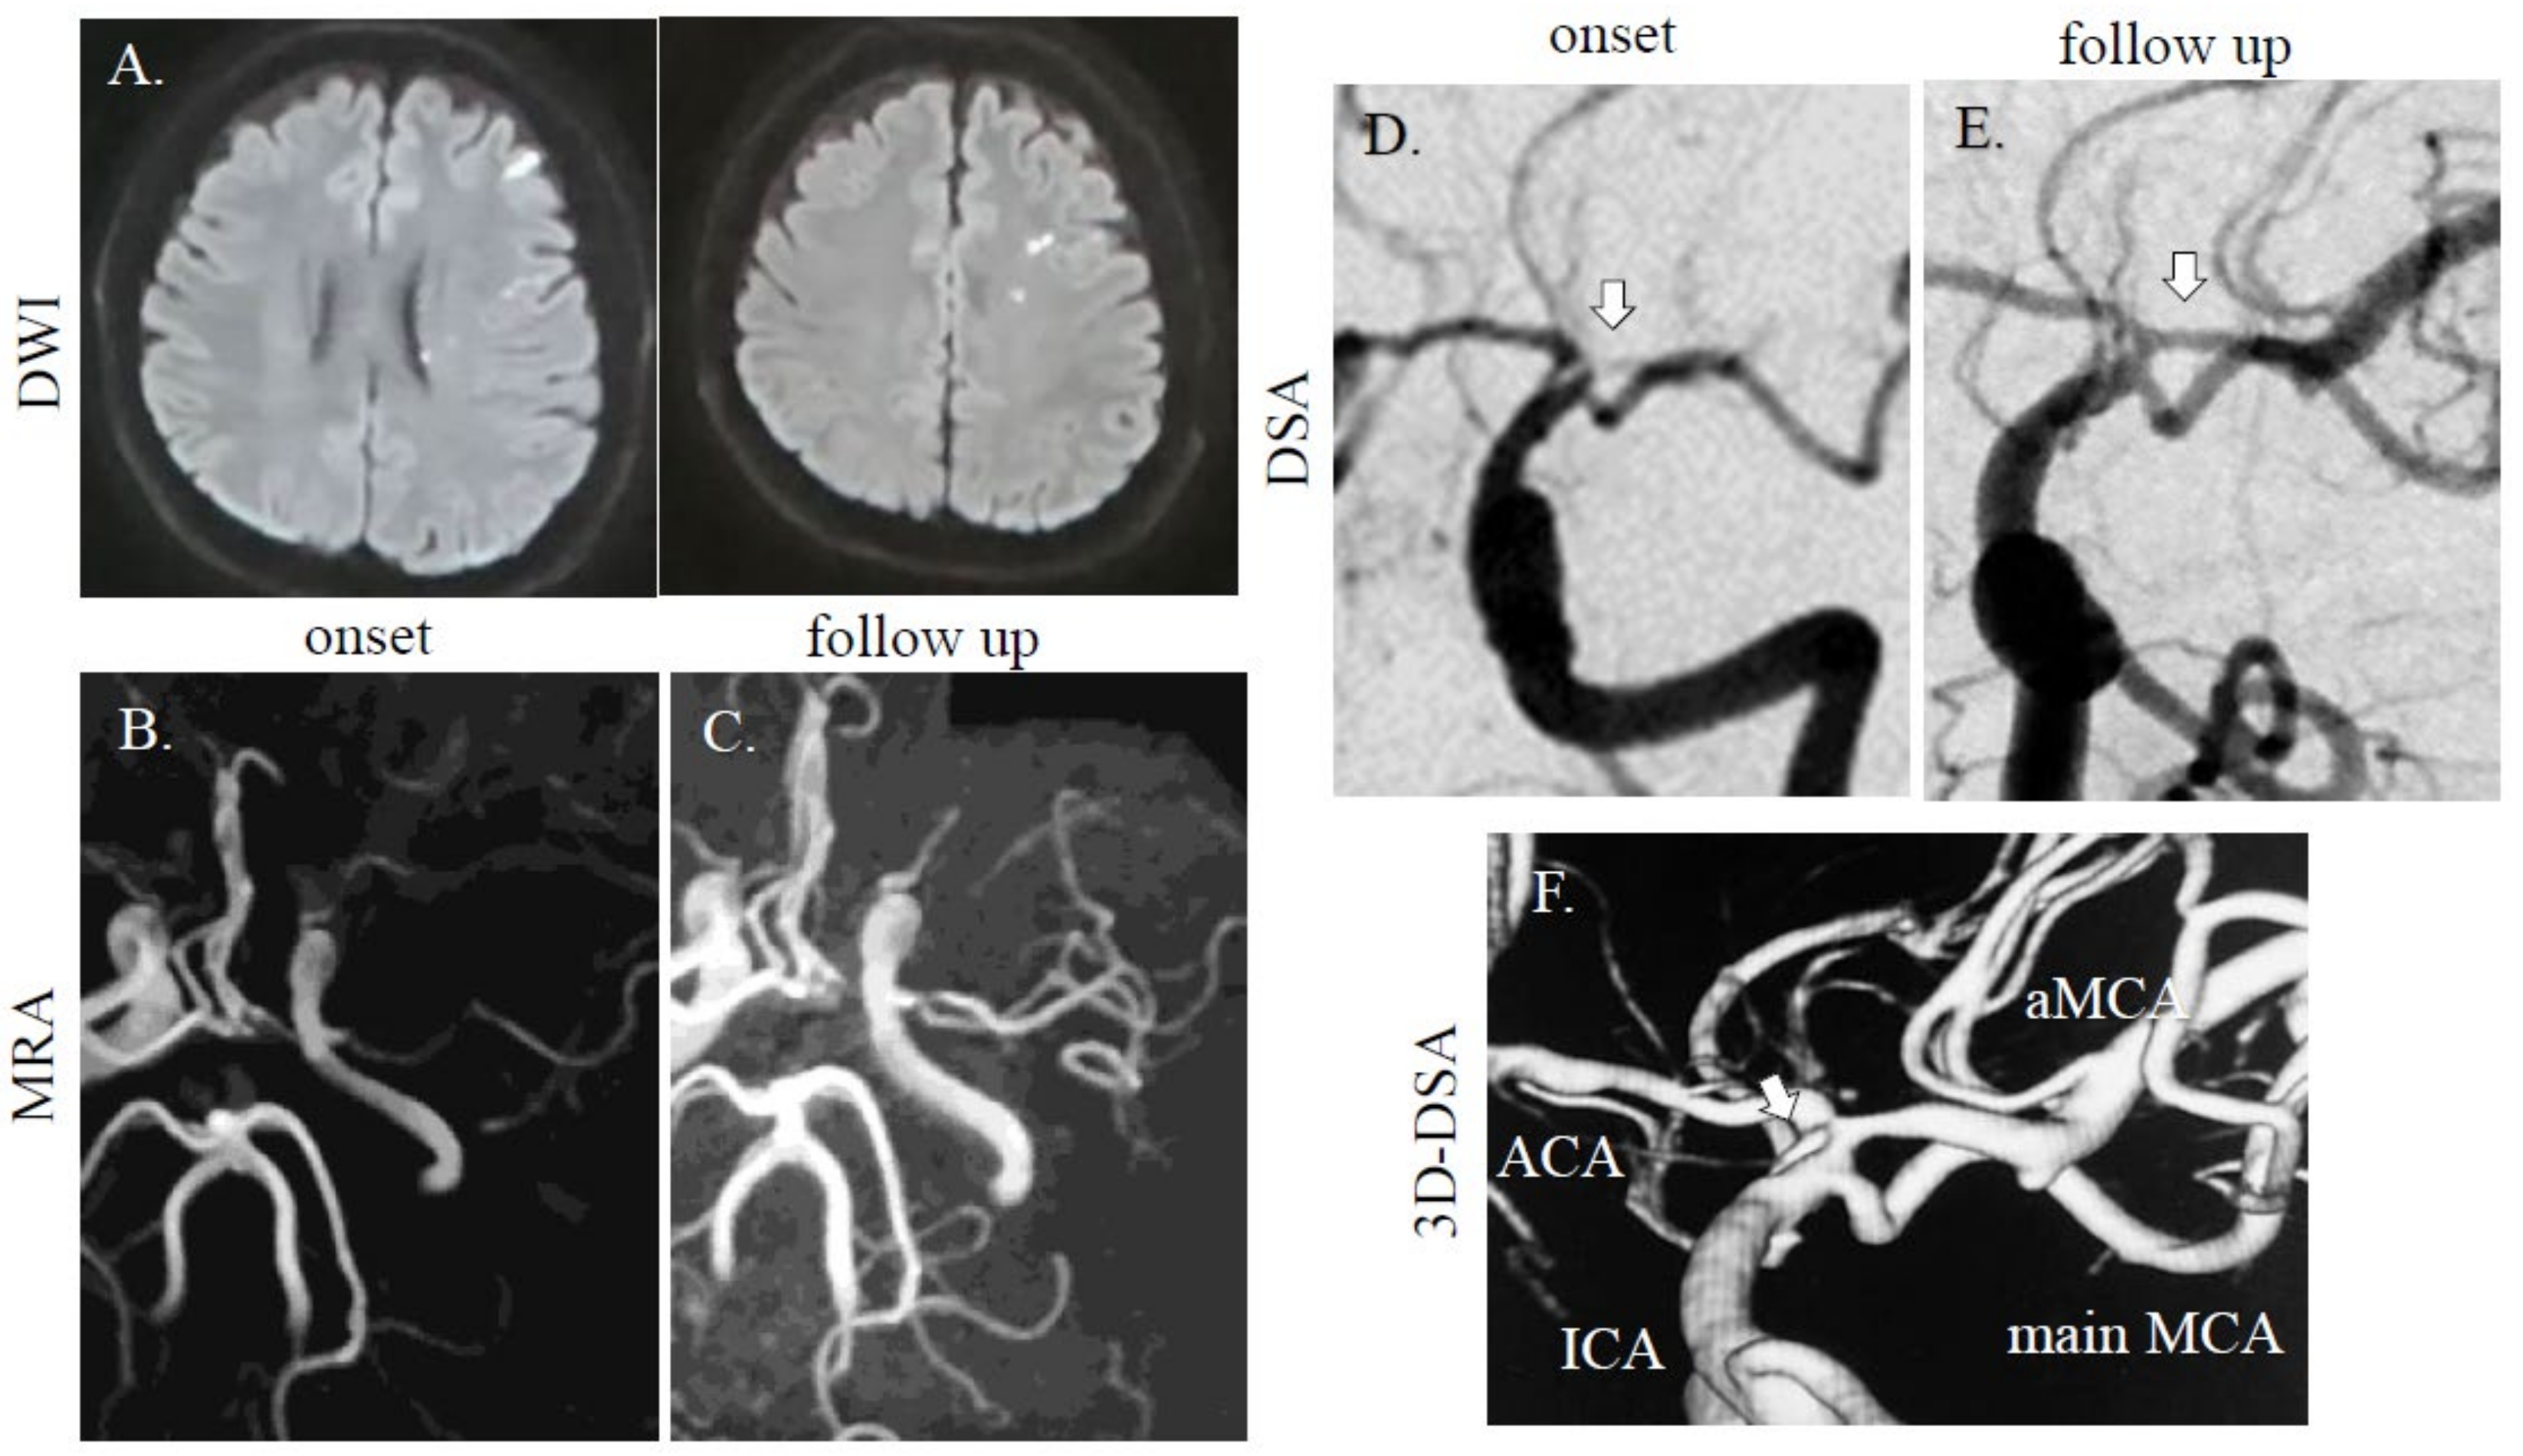

A 40-year-old healthy Asian man with bronchial asthma and no vascular risk factors suddenly developed right hemiparesis and aphasia without headache. He had no history of collagen disorders. He was brought to our hospital 60 min after onset (National Institutes of Health Stroke Scale (NIHSS) score of 16 at arrival; motor aphasia, dysarthria, right facial paresis, and right flaccid hemiparesis), but blood tests were normal including blood coagulation system. Cerebral magnetic resonance imaging (MRI) revealed a dotted acute infarct area in the left hemisphere on diffusion-weighted images (DWI) and string signs were observed at the top of the internal carotid artery (ICA). Distal left MCA flow disappeared due to proximal MCA stenosis on magnetic resonance angiography (MRA) (Figure 1A,B), suggesting cerebral artery dissection. Thrombolytic therapy was prepared. As his symptoms improved after MRI (NIHSS 3; dysarthria, sensory disturbance, and ataxia of the upper limb), thrombolytic treatment was not performed, due to improvement symptoms. On digital subtraction angiography (DSA) for potential thrombectomy, we found a duplicated/accessory MCA. The superior segment was string-like and ended in the anterior cerebral artery (ACA) and the inferior segment continued as the main MCA stem with distal patent branches (Figure 1D); therefore, we were unable to perform thrombectomy. We selected dual antiplatelet therapy (aspirin at 200 mg and clopidogrel at 75 mg with loading on the first day (300 mg)), and intravenous drip of edaravone and hydration, which improved his symptoms. The follow-up MRA/DSA revealed persistent dissection of the left MCA, but with improved distal MCA flow (Figure 1C,E). However, on 3D-DSA, dissection scar was still noted at the origin of the main/accessory MCA (Figure 1F). At discharge, his symptoms were ameliorated. Three months later, he had no neurological deficit.

Figure 1.

MRI/A and digital subtraction angiography (DSA) images of cases 1. (A) A dotted high-intensity area was observed in the left middle cerebral artery (MCA) distal area. In case 1, the left MCA was faint at onset (B), but accessory MCA was noted on follow-up (C) on MRA. On DSA, one intact MCA and one stenotic MCA (arrow) were found (D). In the follow-up study, stenotic MCAs were recovered (E). On 3D-DSA, dissection scar was still noted at origin of main/accessory MCA (F; arrow). Diffusion-weighted images (DWI); repetition time (TR), 7000 ms; echo time (TE), 120 ms. MRA (without using contrast agent); TR, 30 ms; TE, 6.8 ms.